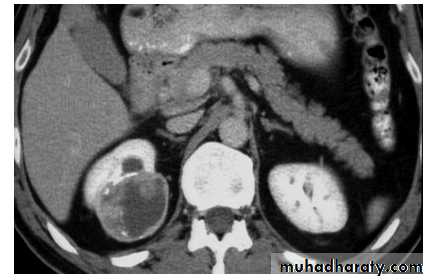

Ct enhanced

Big simple renal cyst(non enhancing mass homogenous) treatment is conservative or drainge if symptomaticWhat's the Diagnosis?